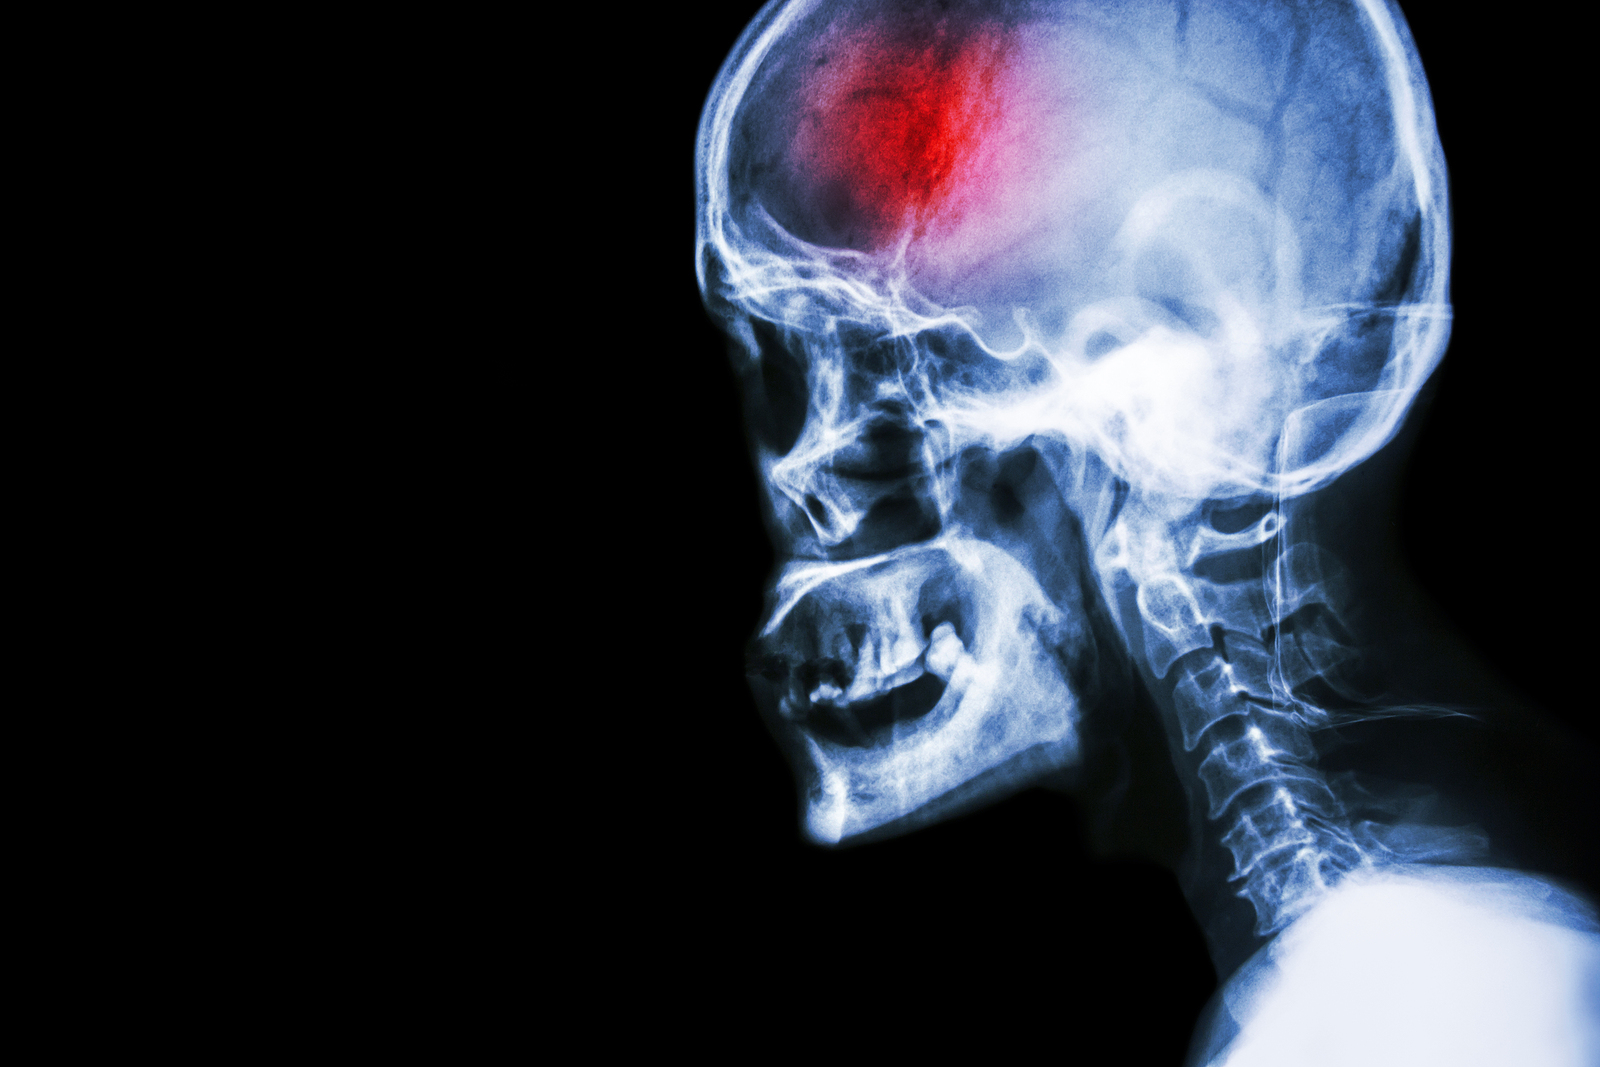

A stroke (previously known as a cerebrovascular accident) when there is a decreased flow of blood to the brain from either a blockage in the blood vessels that supply the brain (ischemic stroke), or a bleed from the blood vessels that supply the brain (hemorrhagic stroke). When the blood flow to the brain is blocked it prevents the brain from getting the needed oxygen and nutrients to function. Without oxygen the brain cells can be permanently damaged or die and the physical and mental functions related to that area of the brain will be affected. A stroke is a medical emergency and rapid treatment is crucial to decreasing the damage caused by a stroke.

- Ischemic stroke: a stroke that is caused by a blockage (clot) that disturbs the blood flow to the brain.

- Hemorrhagic stroke: a stroke that is caused by a bleed that disturbs the blood flow to the brain and puts pressure on the surrounding tissue.

- Transient ischemic attack: often referred to as a “mini-stroke” or TIA, where the blood flow to the brain is temporarily disturbed and as a result causes temporary signs and symptoms of a stroke that resolve quickly .

Computed Tomography (CT) scan and/or Magnetic Resonance Imaging (MRI) scan: These tests are done on your brain and used to locate the exact location of the stroke and to determine if it has been caused by a blockage or a bleed. These tests can also help rule out other conditions that may be causing symptoms, such as an infection or a brain tumour